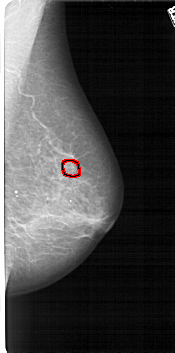

A_1118_1.RIGHT_MLO

RIGHT_CC LINES 4351 PIXELS_PER_LINE 2101 BITS_PER_PIXEL 12 RESOLUTION 43.5 OVERLAY

RIGHT_MLO LINES 5281 PIXELS_PER_LINE 2611 BITS_PER_PIXEL 12 RESOLUTION 43.5 OVERLAY

FILE: A_1118_1.RIGHT_MLO.OVERLAY

TOTAL_ABNORMALITIES 1

ABNORMALITY 1

LESION_TYPE MASS SHAPE IRREGULAR MARGINS SPICULATED

ASSESSMENT 4

SUBTLETY 2

PATHOLOGY MALIGNANT

TOTAL_OUTLINES 1

BOUNDARY